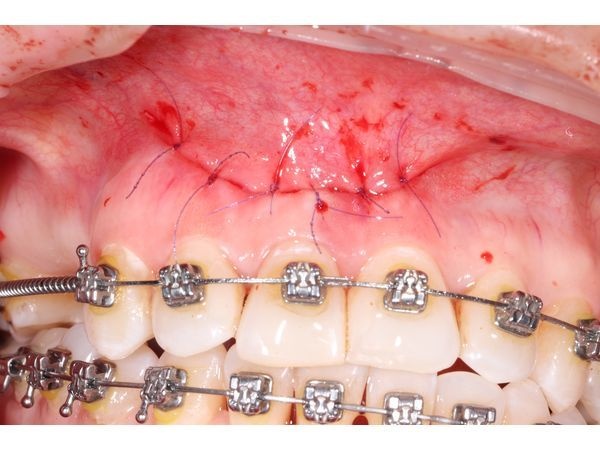

- заполнили ранку PRF-мембраной, богатой тромбоцитами, и ушили слизистую нитью Propylen 5.0.

Через 2 недели пациентка отметила, что ей стало намного лучше, боль прошла. Ей сняли швы: свищевой ход закрылся без следа.